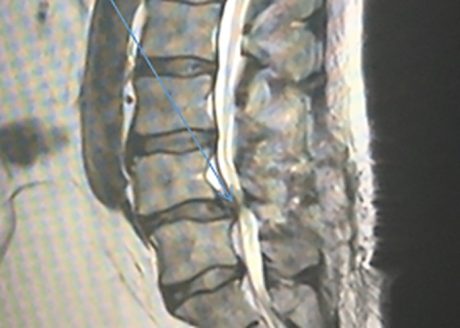

Immediately after the surgery, BL was in great pain, much worse than he had experienced with previous back surgeries. Over the next three days, he began to have difficulty urinating and struggled to walk due to his continuous pain. BL had developed Cauda Equina Syndrome (CES). The surgery undertaken had not created the space anticipated and likely caused CES to develop. The onset of this new condition was a neurosurgical emergency and required an urgent MRI scan and revision surgery.

It is widely accepted that patients experiencing CES must undergo surgery within 24-48 hours of onset if there is to be a good medical outcome. Unfortunately, the CES diagnosis was not made in BL’s case despite the medical records clearly recording “red flag” medical symptoms, such as numbness and pins and needles in the saddle area. Instead, BL was discharged from his private hospital without further investigation. On leaving hospital, BL went home but continued to make calls to his surgeon and his GP as he continued to experience significant pain, numbness and pins and needles. He struggled to walk.

Ultimately, BL was asked by his private neurosurgeon to attend his local NHS hospital for a new scan. There was a further delay at that stage, with the NHS hospital failing to recognise the urgency of BL’s condition.